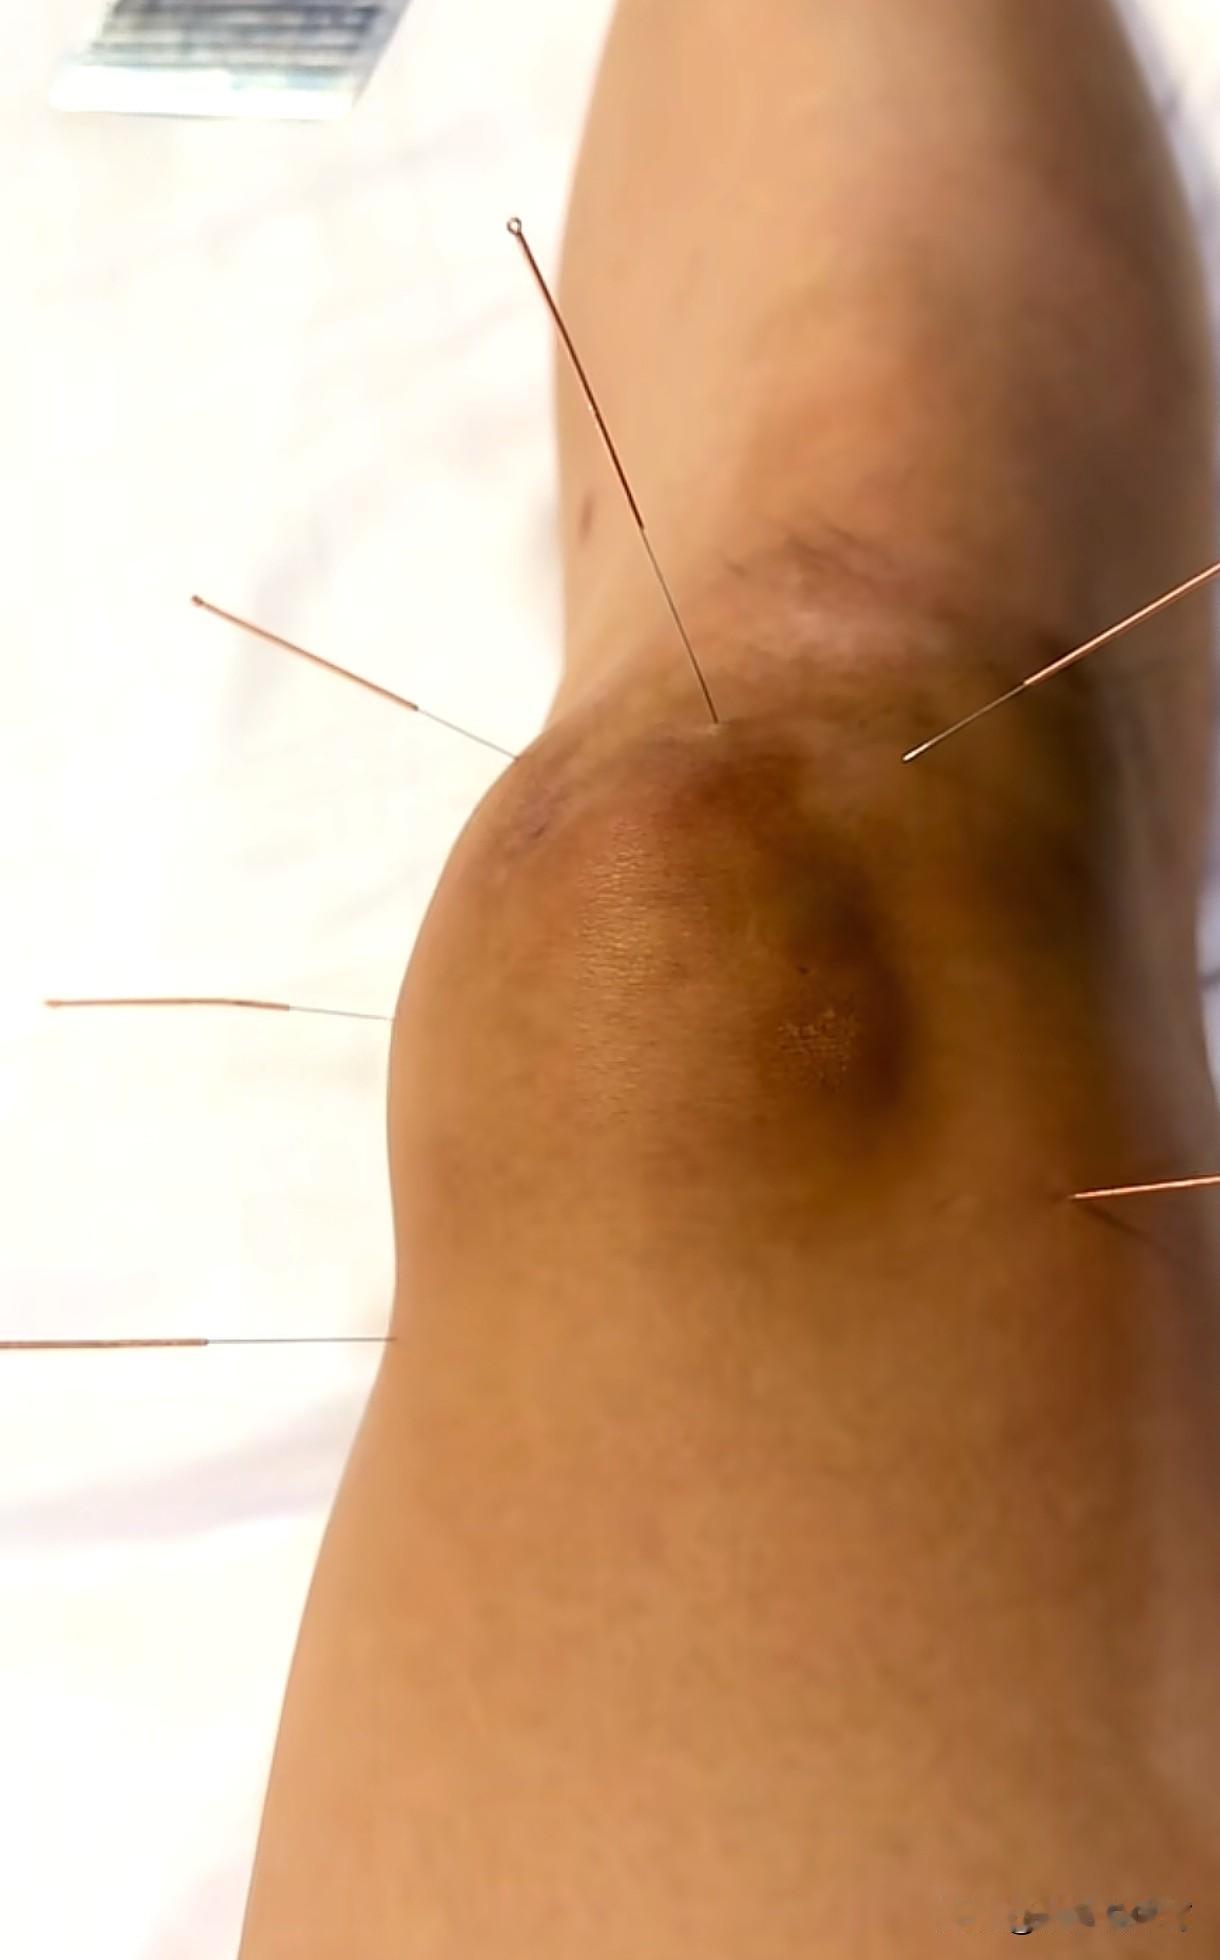

天津女排大将王艺竹透露自己打了封闭出战全运会。伤痕累累的王艺竹发布了自己的治疗和康复训练的图文视频,看了很心酸。当然,作为职业球员,这是常态,但她也不过是20多岁的小女生,却是一身伤病,甚至还打了封闭针出战比赛。封闭的副作用非常巨大,对于人体而言是不可修复的一种伤害,但是为了天津女排的成绩、回馈对于自己的培养,也是出于她个人的职业担当和态度,她毫不犹豫选择了承受和忍耐。如今的王艺竹是天津女排的中流砥柱,在李盈莹、王媛媛“留洋”之后,她和陈博雅将是天津女排的核心力量。距离新赛季联赛揭幕还有不到一个月的时间,王艺竹需要尽快康复,投入新的战斗。